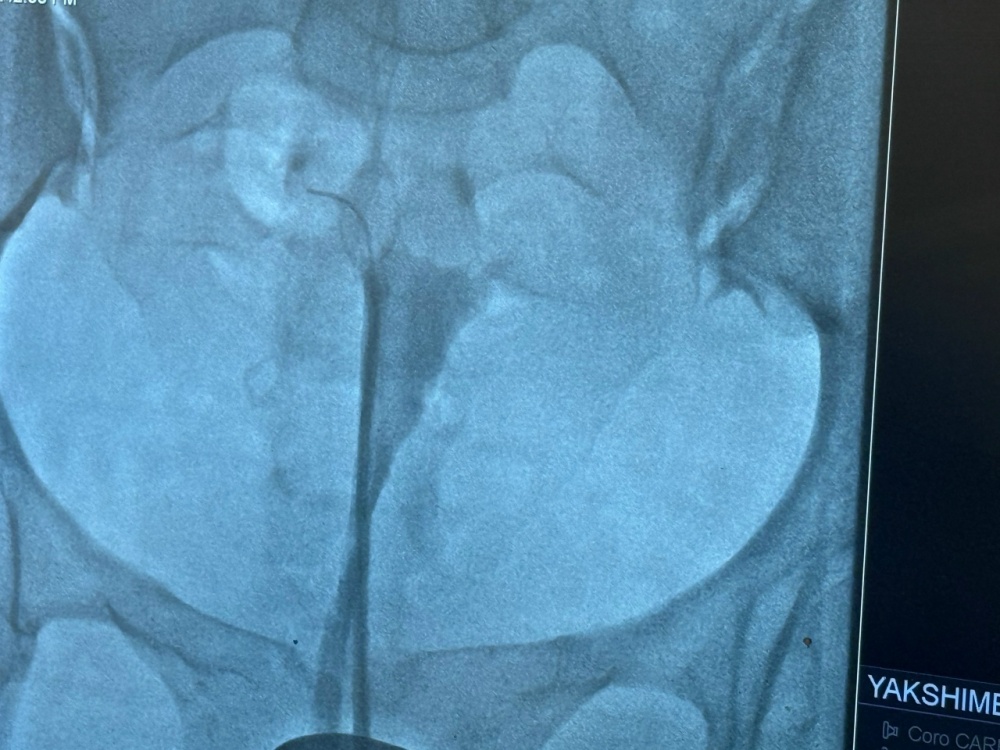

В Белорецкой ЦРКБ рентген- сосудистые хирурги совместно с гинекологами впервые провели операцию - реканализацию маточных труб! Все прошло успешно для нашей пациентки! Показания к данной операции является бесплодие ,трубный фактор-это патология, вызванная непроходимостью или нарушением функции маточных труб, из-за чего яйцеклетка не встречается со сперматозоидом, что составляет около 20–30% случаев женского бесплодия. Данная операция будет проводиться по записи после обследований и врачебной комиссии совместно с рентгенолог-сосудистыми хирургами. Будьте здоровы!!!